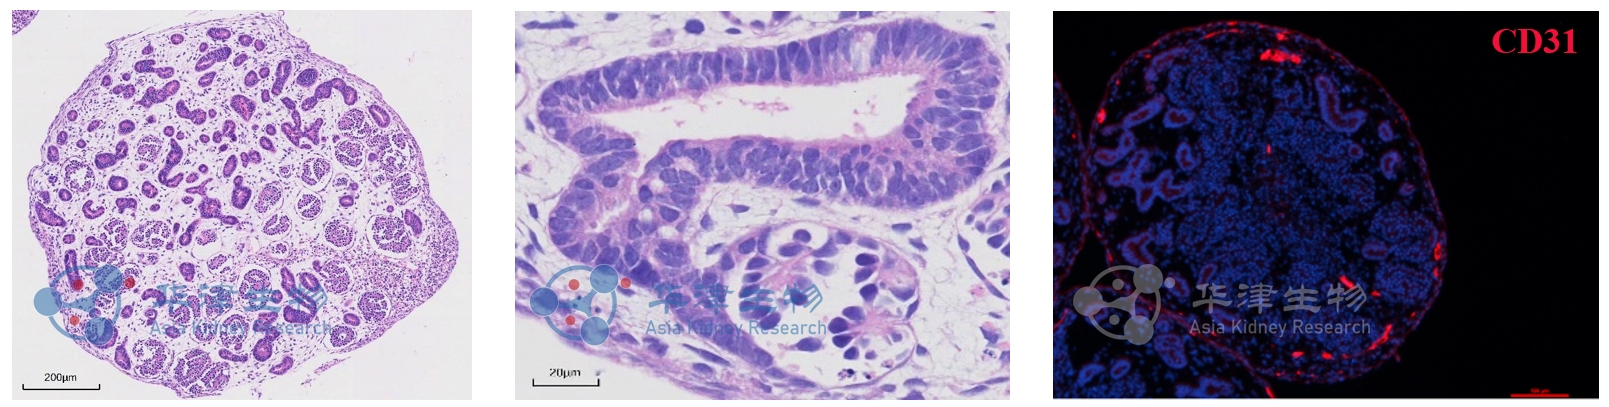

图3. 经病理切片图和荧光染色图鉴定,Kidnioid®技术平台构建的肾脏类器官包含肾小球、肾小管及血管样结构